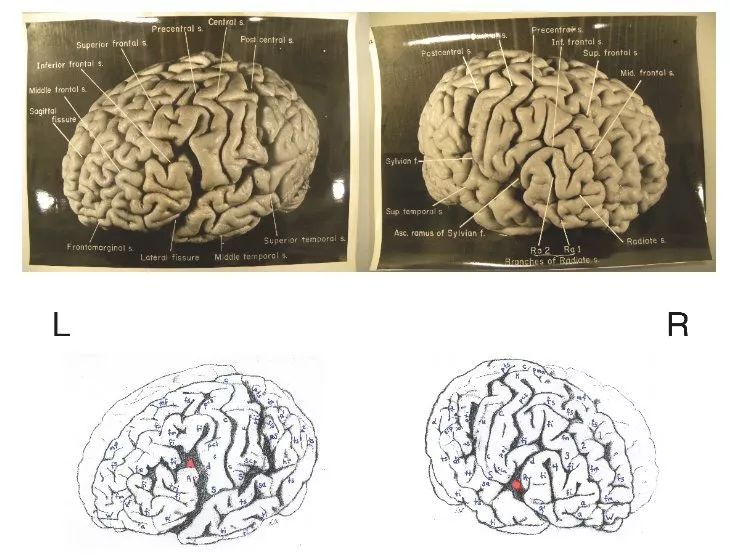

↑ 爱因斯坦的左右脑

人们极力在爱因斯坦的大脑中寻找特殊之处,但除了发现他的两个半球的下顶叶区域(涉及到处理数字的能力)比平均值稍大一些之外,没有超出正常程度的偏差。科学家沮丧地一无所获,他的大脑太正常了——这简直不太正常。